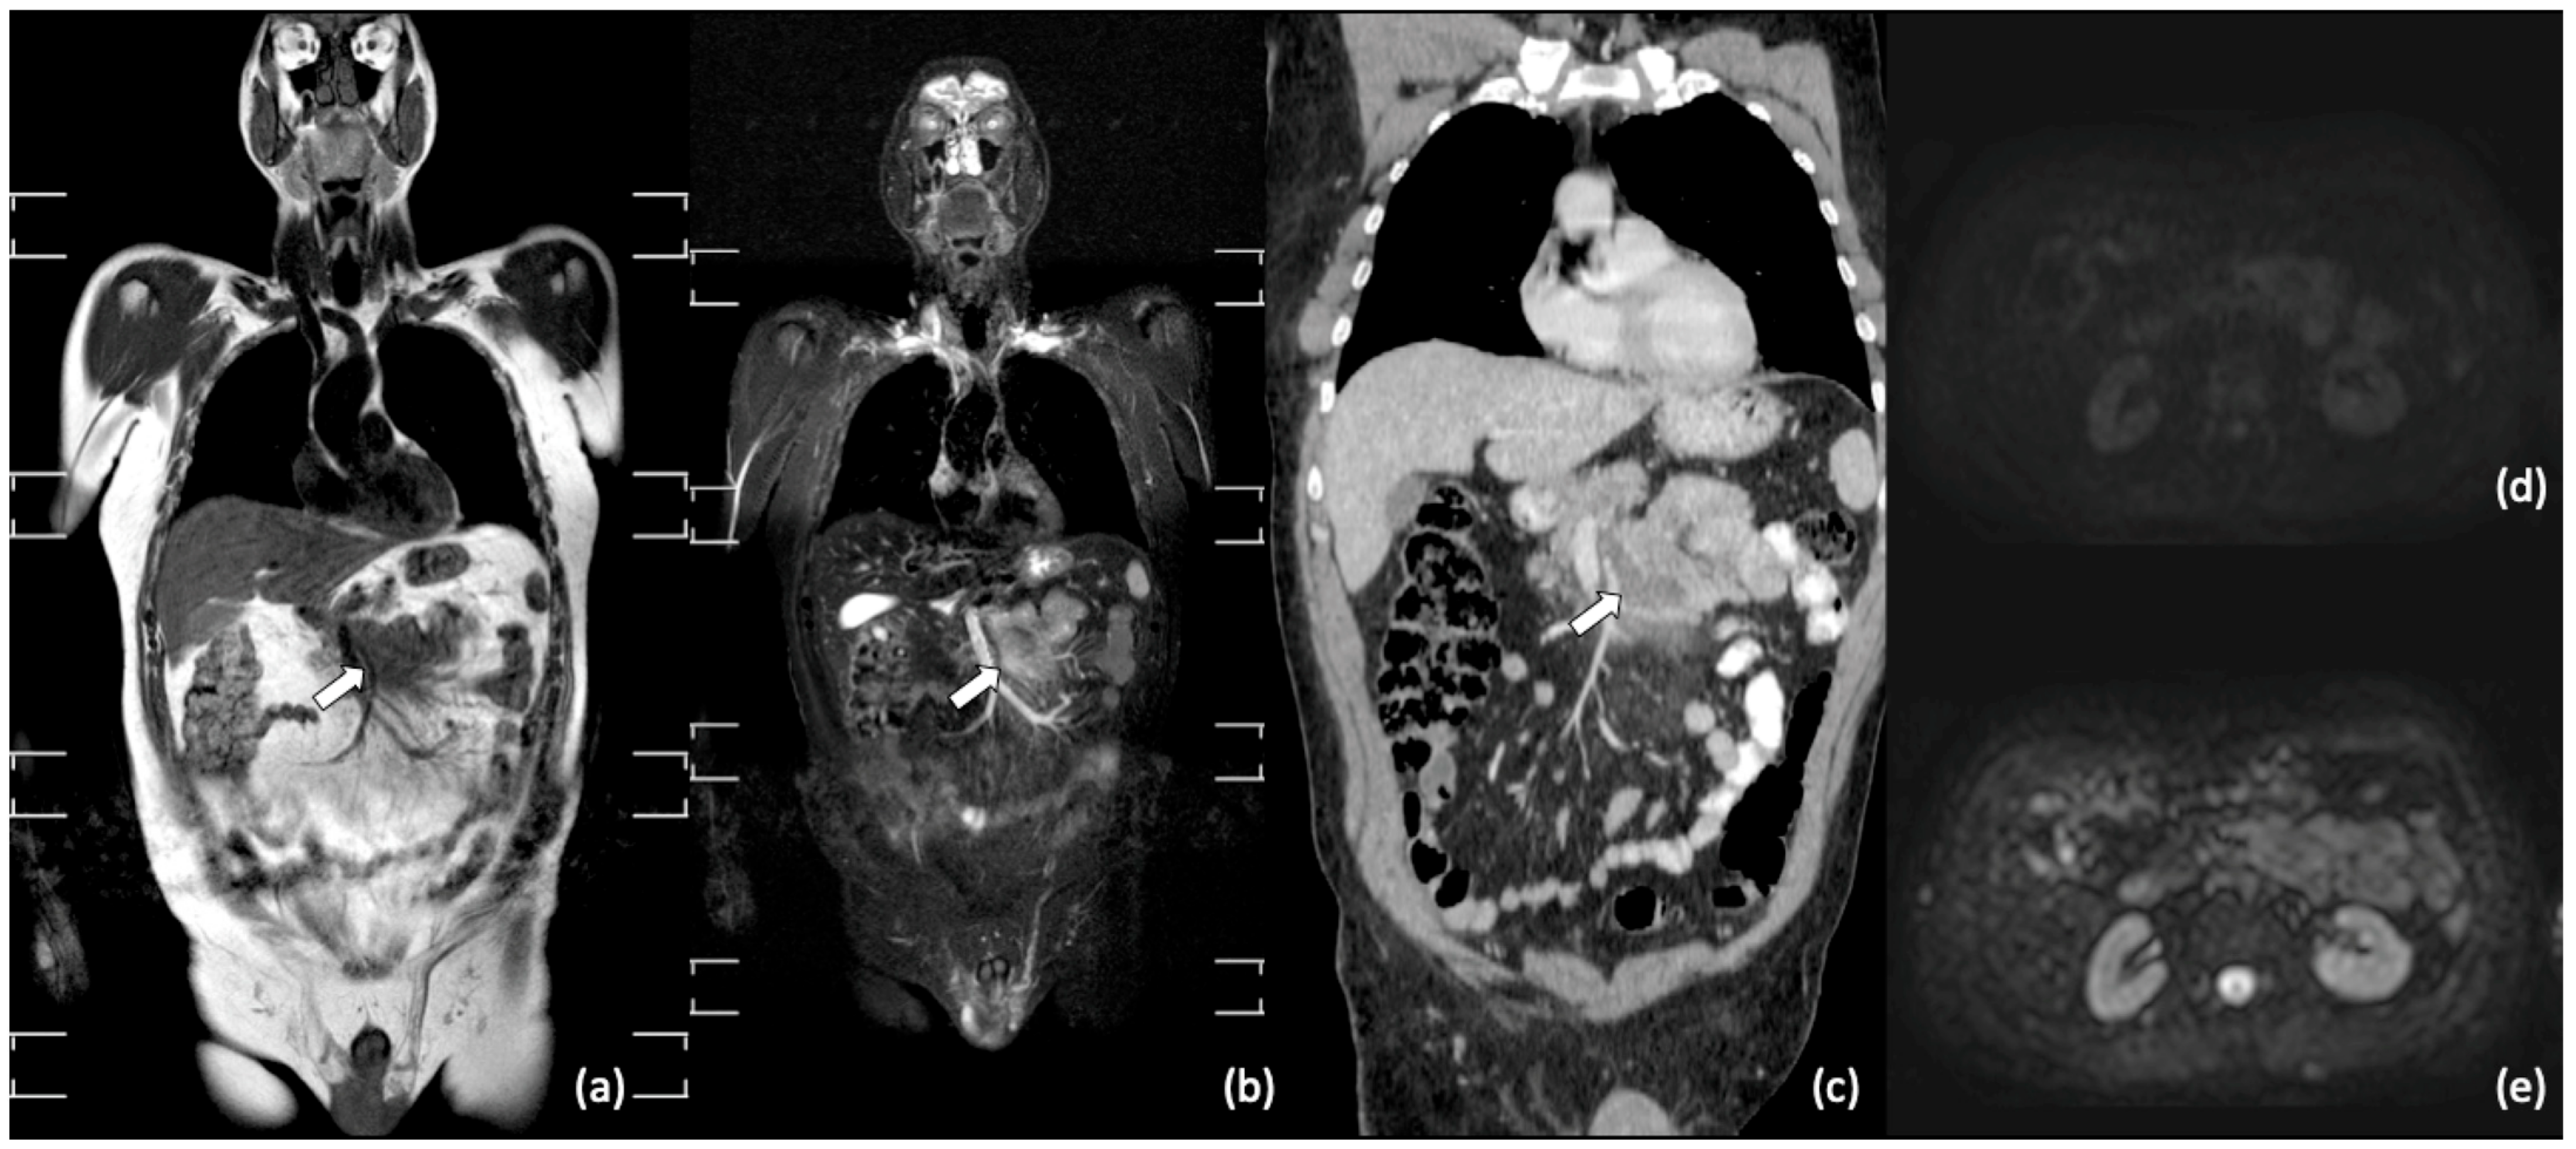

- Albano, D.; Patti, C.; La Grutta, L.; Agnello, F.; Grassedonio, E.; Mulè, A.; Cannizzaro, G.; Ficola, U.; Lagalla, R.; Midiri, M.; et al. Comparison between whole-body MRI with diffusion-weighted imaging and PET/CT in staging newly diagnosed FDG-avid lymphomas. Eur. J. Radiol. 2016, 85, 313–318. [Google Scholar] [CrossRef] [PubMed]

- Lin, C.; Luciani, A.; Itti, E.; El-Gnaoui, T.; Vignaud, A.; Beaussart, P.; Lin, S.-J.; Belhadj, K.; Brugières, P.; Evangelista, E.; et al. Whole-body diffusion-weighted magnetic resonance imaging with apparent diffusion coefficient mapping for staging patients with diffuse large B-cell lymphoma. Eur. Radiol. 2010, 20, 2027–2038. [Google Scholar] [CrossRef]

- Stecco, A.; Buemi, F.; Quagliozzi, M.; Lombardi, M.; Santagostino, A.; Sacchetti, G.M.; Carriero, A. Staging of Primary Abdominal Lymphomas: Comparison of Whole-Body MRI with Diffusion-Weighted Imaging and18F-FDG-PET/CT. Gastroenterol. Res. Pr. 2015, 2015, 1–8. [Google Scholar] [CrossRef] [PubMed]